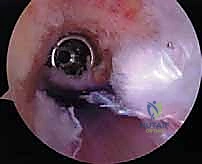

- الجراحة المجهرية وتنظير المفاصل بدقة 4K: يستخدم الدكتور هطيف أحدث تقنيات مناظير الركبة (Arthroscopy) المزودة بكاميرات عالية الدقة 4K، مما يتيح له رؤية أدق التفاصيل داخل المفصل، وتشخيص الأضرار المجهرية، وإجراء الجراحة بأقل تدخل جراحي ممكن (Minimally Invasive).